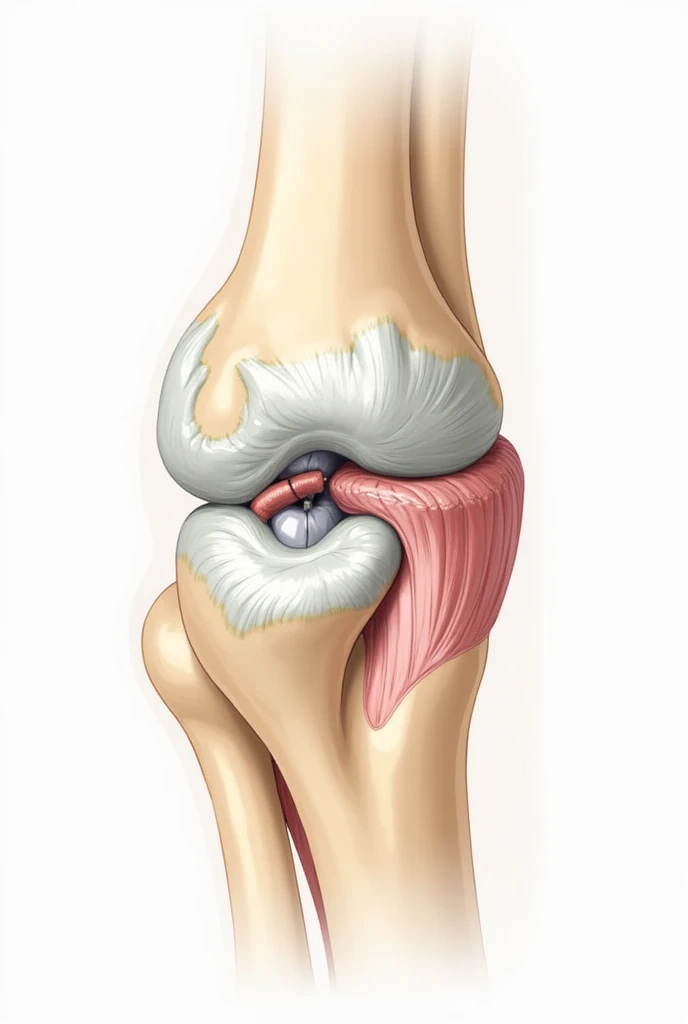

Close-up of human knee,There is a bone in the middle, knee, Knees, surreal bone structure, Protruding bones, Realphotos, orthographic view, Look across the shoulder, medical depiction, Osteoarticular joints, computer generated, hyper realisitc, sharp bone structure, joint, digital painted

medical depiction

Osteoarticular joints

joint